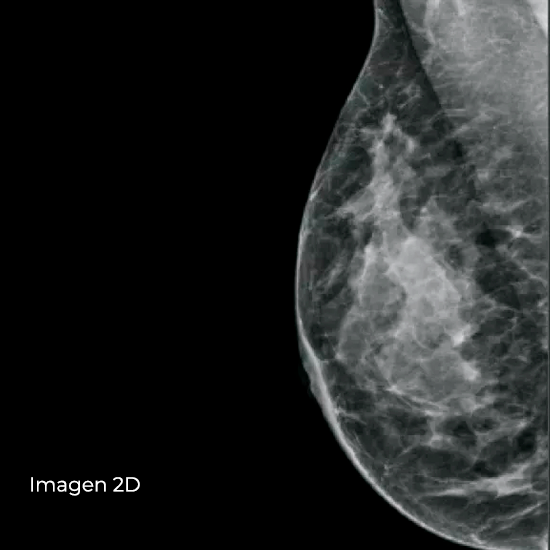

Cree estudios de diagnóstico integrales con un nivel de detalle clínico y una sensibilidad excepcionales mediante la técnica de obtención de imagen en 2D con contraste (CE2D). Esta herramienta avanzada combina los estudios de CE2D y 3D Mammography™ para mejorar la capacidad de identificar cánceres precozmente.

Se ha demostrado que la mamografía con contraste permite detectar cánceres que no se ven claramente en una mamografía convencional. La combinación de la obtención de imagen en 2D con contraste (CE2D) y una exploración por tomosíntesis permite la localización y la evaluación morfológica de las lesiones, lo que potencia el valor del procedimiento de CE2D en la identificación de posibles tumores malignos.

Modo Combo CE2D: 2D con contraste + Imagen en 3D™